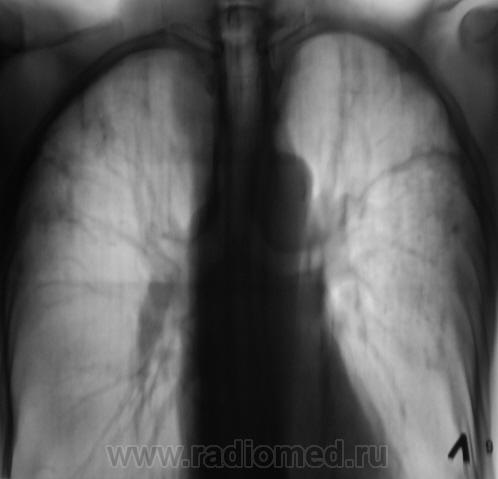

Диссеминированный ТБС, фаза инфильтрации... и хронический бронхит.

То. что ТБС - сомнений не вызывает. А вот какой - пусть разбираются фтизиатры, главное больного отправить по правильному направлению. Там и каверны и диссеминация...

ПОХОЖЕ НА  2-Х СТОРОННИЙ  СПЕЦИФИЧЕСКИЙ  ПРОЦЕСС.

С  2-Х СТОРОН   В  ВЕРХНИХ ОТДЕЛАХ  НА  ФОНЕ  ПНЕВМОФИБРОЗА МНОЖЕСТВЕННЫЕ

ОЧАГОВЫЕ ТЕНИ. ХОРОШО  БЫ  ВЗГЛЯНУТЬ НА  РЕНТГЕН- АРХИВ.

Выражен пневмофиброз в верхних и средних отделах легких, с наличием очаговоподобных теней преймущественно средней плотности. Нижние поля эмфизематозные. Корни структурные, содержат мелкие кальцинаты лимфоузлов ( не люблю выражение "фиброзно изменены"). Cor вертикального положения. Неплохо-бы узнать профмаршрут больного. В диф. ряд должны быть включены фиброзирующие процессы легких (основные-альвеолит, пневмокониоз, ТБС). Показано УЗИ щитовидной железы.

Вот такой случай. Пациент на учете по поводу фиброзно-кавернозного туберкулёза.

Сомнения вызвала тень, помеченная желтой стрелкой. На наш взгляд, это был растущий гриб. Однако возобладало мнение, что "это" участок некроза, так как не было "симптома погремушки"

Однако, в последующем, лабораторно наличие "гриба" было доказано.

И, уже через год, при плановом обследовании данного пациента, мы "поимели" такие картинки.